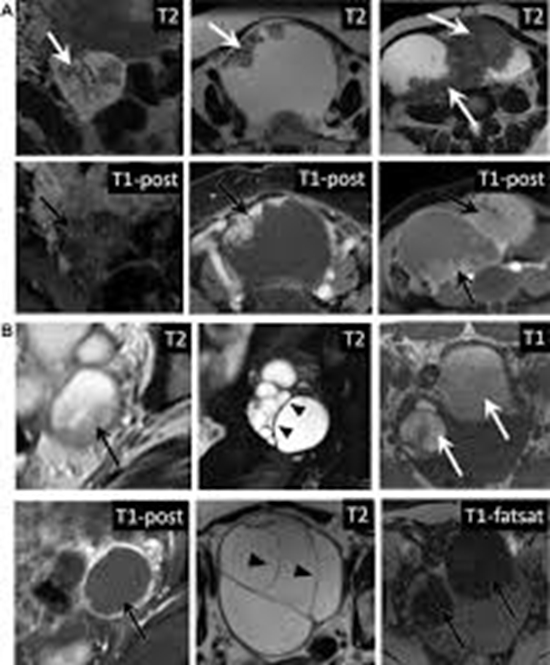

بررسی میزان توافق مابین ADNEX MRI scoring system با sonographic modified ORADS در افتراق توده های تخمدانی در Dynamic contrast enhanced MRI کد خبر : 293227 کپی کلمات کلیدی توده_های_تخمدانی_dynamic_contrast_enhanced_mriadnex_mri